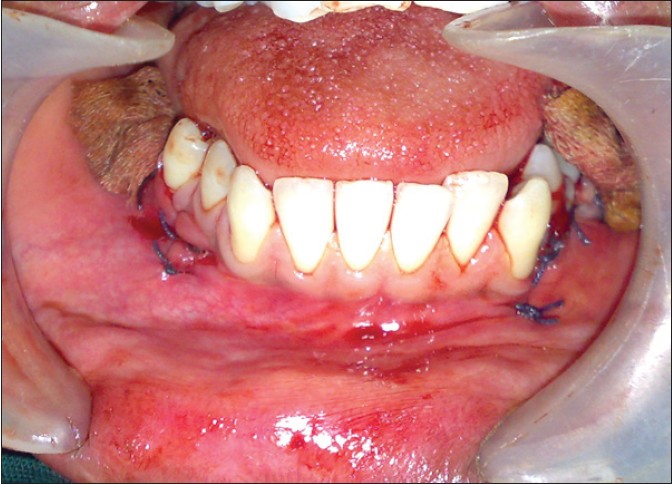

Under general anesthesia the cystic lesions in all four quadrants were enucleated along with impacted third molars and supernumerary teeth. Also in both quadrants of mandible extraction of the first and second molars were carried out as they were mobile. The resultant cavities [Figure 10] in the mandible after enucleation were packed with bismuth, iodoform, paraffin paste, and healing was by secondary intention [Figure 11]. Follow-up dressing was done after 24 hours postoperatively for the first 2 weeks and then follow-up of intraoral wound irrigation and dressing was carried out once a week for next 2 months for healing of the bony defects in mandible intraorally. Postoperative follow-up orthopantomographs (OPGs) were taken at regular monthly intervals. Six months postoperatively the dimensions of the cystic cavity were reduced both clinically and radiographically [Figure 12] and [Figure 13]. The patient is still under routine follow-up and will be closely monitored for long-term outcome. | Figure 10: Intraoperative clinical photograph showing resultant bony cavities after enucleation of dentigerous cysts in mandible

Click here to view |

| Figure 11: Postoperative clinical photograph showing the gauze packed in to the bony cavities after cyst enucleation

| Figure 12: Intraoral clinical view after 6 months showing the healing of bony cavities